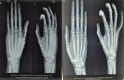

Case report: We have included five cases of osteochondromas occurring at rare locations with variable presentations and their management. We have included one case of metacarpal, one case of skull exostosis, two cases of scapula exostosis, and one case of fibula exostosis.